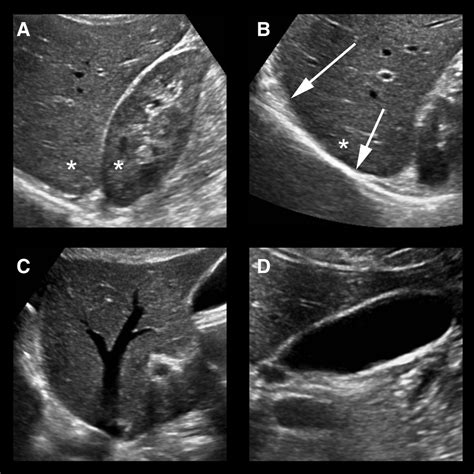

If the ultrasound reveals any abnormalities, further diagnostic tests may be recommended. These could include:

• Blood Tests: To assess liver function and detect any underlying conditions.

• CT Scan or MRI: For more detailed imaging of the liver and surrounding structures.

• Biopsy: In some cases, a liver biopsy may be necessary to confirm a diagnosis.

While a normal liver ultrasound is the desired outcome, there are several common findings that may be detected during the procedure. These include:

• Cysts: Fluid-filled sacs that can form in the liver. Most cysts are benign and do not require treatment.

• Tumors: Abnormal growths that can be benign or malignant. Further testing is usually required to determine the nature of the tumor.